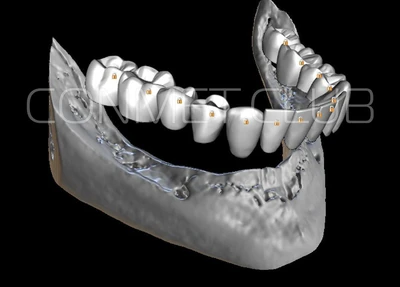

2. После этого произвели компьютерное моделирование самого имплантата и фиксирующих элементов. Примечательно, что в абатментах, использовался отлично зарекомендовавший себя и проверенный десятилетиями интерфейс КОНМЕТ! В результате получили несколько специальных файлов, позволяющих не только сделать сам имлантат, но еще до операции изготовить и сами зубы. Данные файлы передали в изготовление на специальном 3D оборудовании.

Имплантат напечатали из особого, биосовместимого, медицинского титана на предприятии имеющим соответствующую медицинскую лицензию. Толщина имплантата составила 0,8 мм, а вес всего несколько грамм!

Первый вывод к которому мы пришли, это то, что для данных конструкций имплантатов сохранять внутренний интерфейс с шестигранником и конусом Морзе нецелесообразно из-за ограничения возможностей современной 3D печати титана. Кроме того, техническая обработка после 3D печати такого интерфейса представляет значительные трудности и ведет к неоправданному увеличению цены. Поэтому пришли к единодушному мнению, что лучший вариант-это опорные элементы полностью повторяющие абатменты-мультиюниты.

Второй, и наверное главный вывод-решение - моделированием и конструированием индивидуальных, субпериостальных имплантатов должен заниматься инженер-конструктор с большим опытом в медицине и знаниями индивидуальной анатомии челюстно-лицевой области на уровне хорошего хирурга. При этом все-равно должно осуществляться тесное и постоянное взаимодействие с хирургом, который будет проводить операцию.

Посмотрите на приведенные выше работы и вы обратите внимание, что перфорации в теле имплантатов подчиняются скорее "художественным" принципам нежели биомеханическим. Поэтому уже в 2018 году не только изготовление, но и конструирование имплантатов было целиком передано сотрудникам Конмет. Это в значительной степени повысило качество самих имплантатов, но по вполне понятным причинам (таких грамотных инженеров-конструкторов по определению не может быть много) резко удлинились сроки изготовления. При определенных случаях, когда после удаления зубов кость еще не окончательно закончила ремоделировку, срок с момента КТ по которому моделируют субпериостальный имплантат, до операции может носить критический характер. Т.е., чем дольше время изготовления, тем больше вероятность того, что имплантат не полностью будет соответствовать рельефу подлежащей костной ткани.

Посмотрите на небольшом клиническом примере новый подход к конструированию имплантата по сравнению с имплантатами описанными в начале этой статьи.